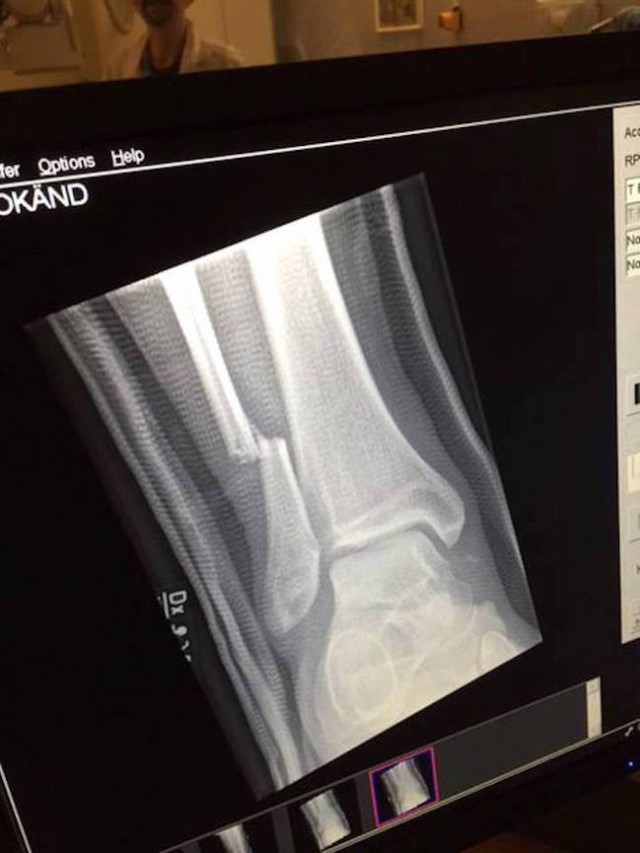

Le conseguenze sono un po’ più gravi, come si può vedere dalla lastra qui sotto.